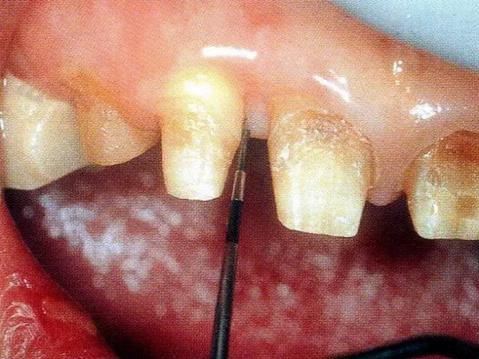

▼圖13-1 近中顎側(cè)術(shù)前牙周探診值是8mm。